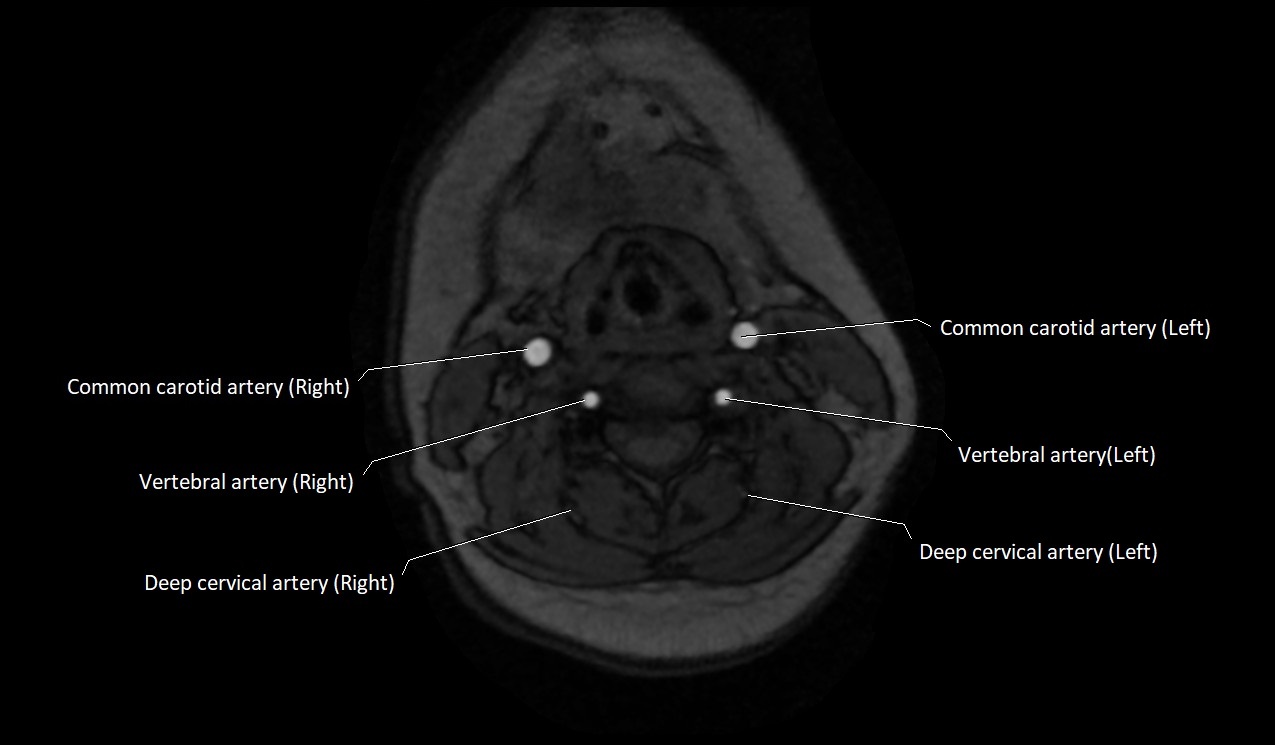

MRI Appearance:

• T1-Weighted Images:

• Appears as a tubular, hypointense (dark) structure relative to muscle

• May show flow void if the blood flow is fast

• T2-Weighted Images:

• Typically hypointense or isointense to muscle, but can be hyperintense if slow flow or stasis is present

MRI images

image